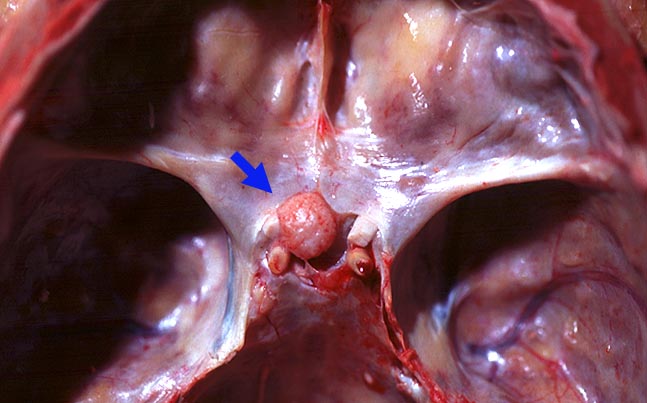

Meningeom des Tuberculum sellae

Meningeom des Tuberculum sellae auf der Mittellinie, leicht nach links verschoben liegend. Feinhöckrige Oberfläche. Leichte Verformung des Nervus Opticus sinister kurz vor Eintritt in den Canalis opticus.

Berührung der Arteria cerebri media ohne Verformung und dorsale Verlagerung des Hypophysenstiels durch das Meningeom. Histologisch Meningeom vom transitionalen Typ.